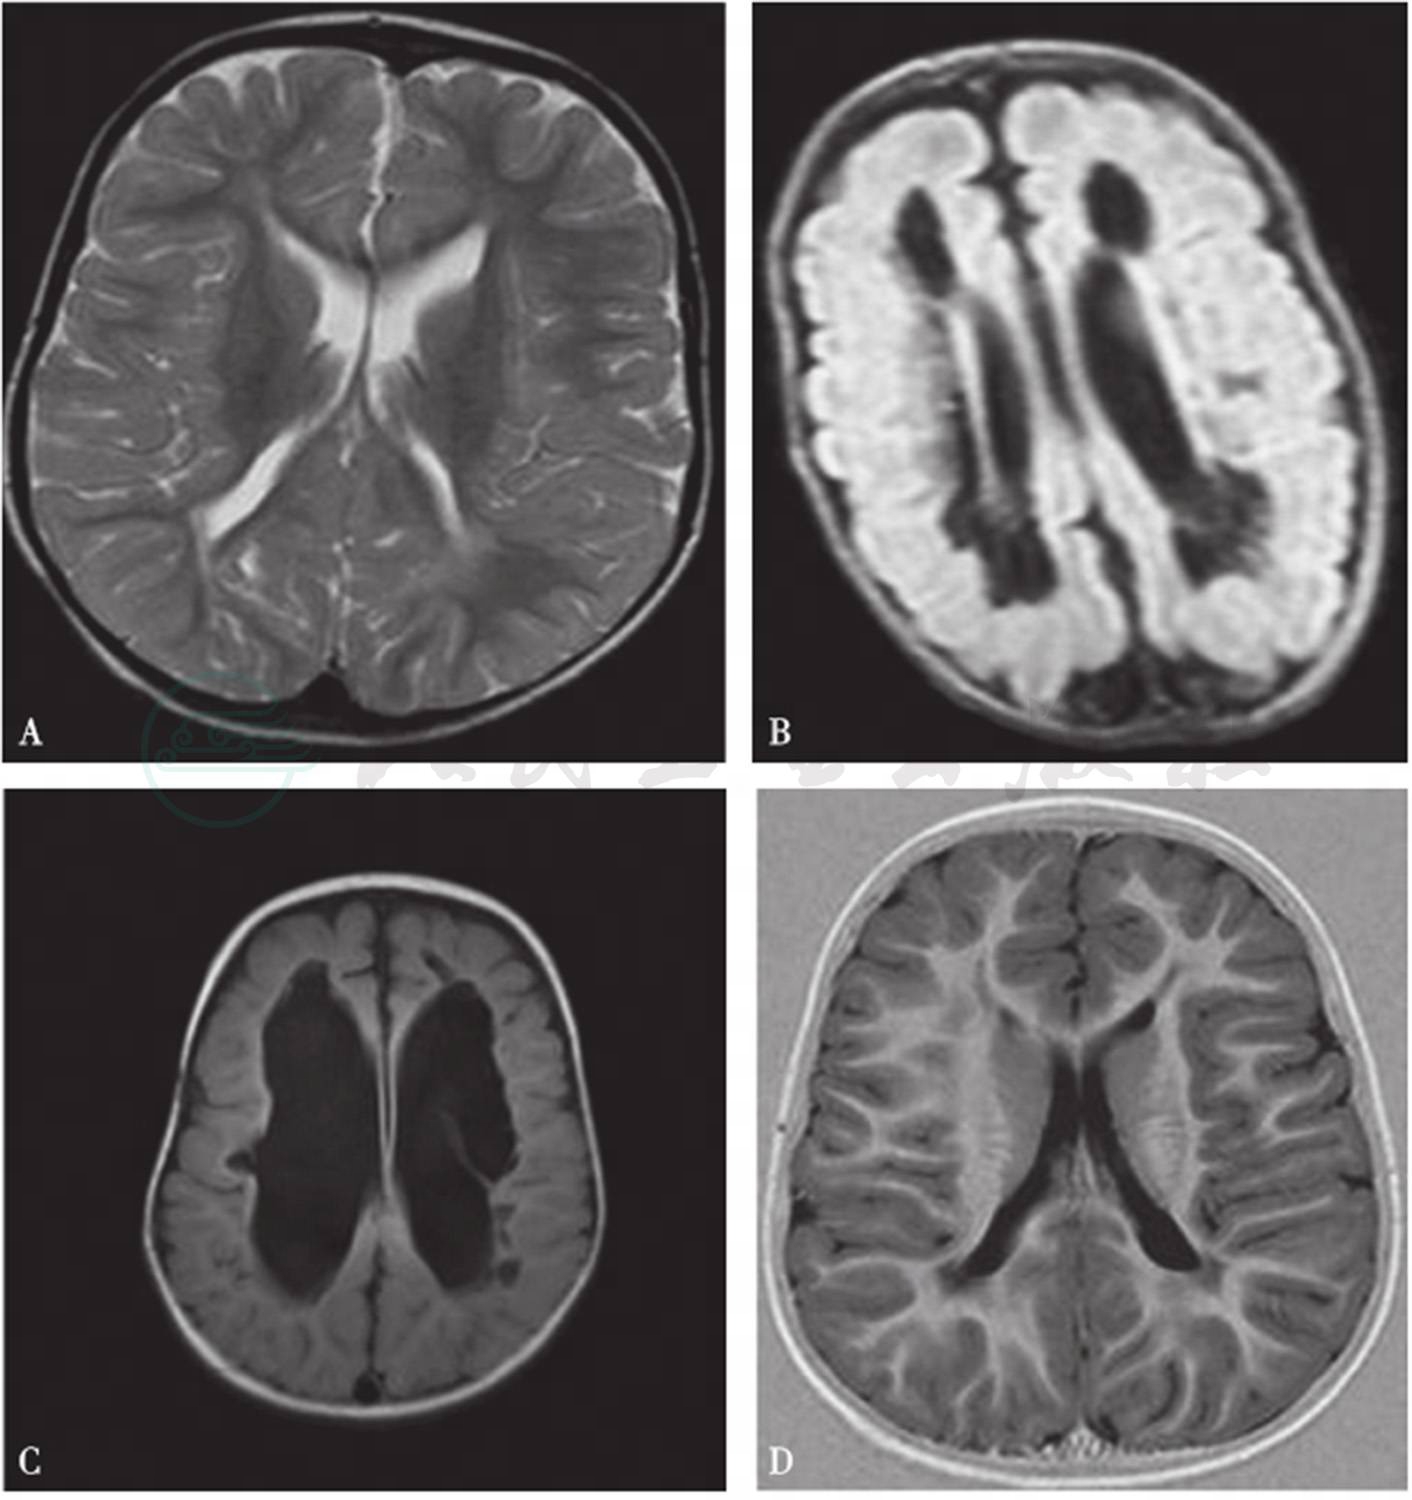

2.MRI

MRI的分辨率高于超声,尤其是不断进展的检查序列有利于对早产儿脑白质损伤的诊断,可在病变早期精确描述病变位置,损伤范围和病变类型(图3)。

(1)白质损伤不同时间的影像特点

1)早期

常规的T1WI可显示脑室旁低信号损伤,T2WI则显示高信号,较前者更为敏感。

2)后期

T1WI和T2WI均可显示PVL形成,以及损伤后期脑室增宽。脑室增宽是脑白质丢失的结果,伴胶质细胞增生,形成瘢痕,皮层减少,在MRI T1WI显示清晰,脑室宽而壁不规则,信号增强,同时皮层脑沟异常加深,与脑室接近,胼胝体变薄。显示了脑室旁和更广泛的灰白质损伤的结局,是遗留后遗症小儿脑内组织解剖基础[5]。

图3脑白质损伤的MRI影像

A.脑室旁T2高信号;B,C.脑室旁软化灶,不同程度脑室增宽;D.脑室变形,脑沟加深,脑白质不规则丢失

引自:实用新生儿学.第5版.ISBN:978-7-117-27403-6.主编: